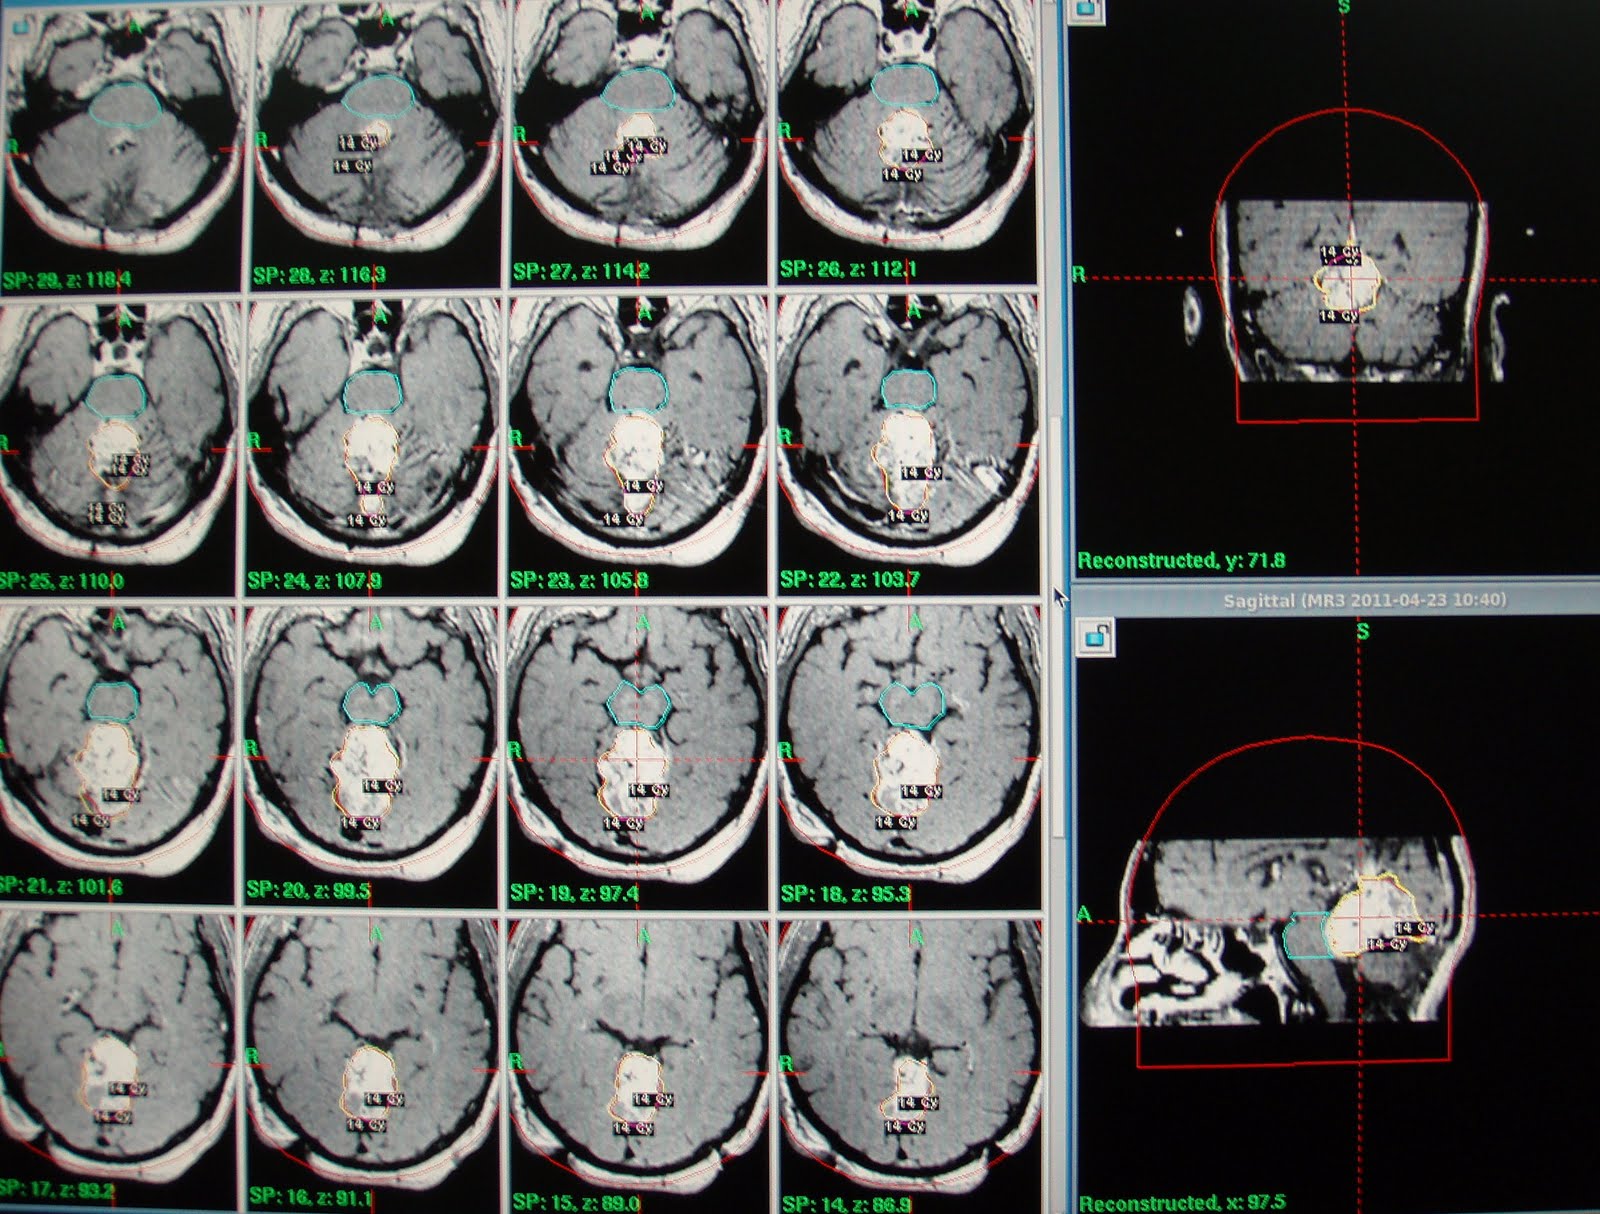

On referral for Gamma Knife, MRI brain with contrast shows the recurrent multilobulated midline extra axial mass  occupying the supracerebellar cistern, encroaching into quadrigeminal cistern besides bulging into upper 4th ventricle.Mass was compressing upon adjacent faces of occipital lobes and superior vermis / adjacent cerebellum. He was treated with 14 Gy at 50% IDL for a Vol. of 27.8 cc. with multiple isocenters.

At GKRS